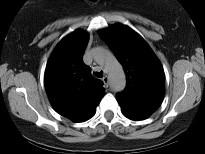

问题 男,68岁,呼吸困难、轻度吞咽困难3月余,请结合CT,选择最可能的诊断 ( )

选项 A.气管乳头状瘤 B.气管脓肿 C.气管炎性假瘤 D.食管癌 E.甲状腺癌

答案 A